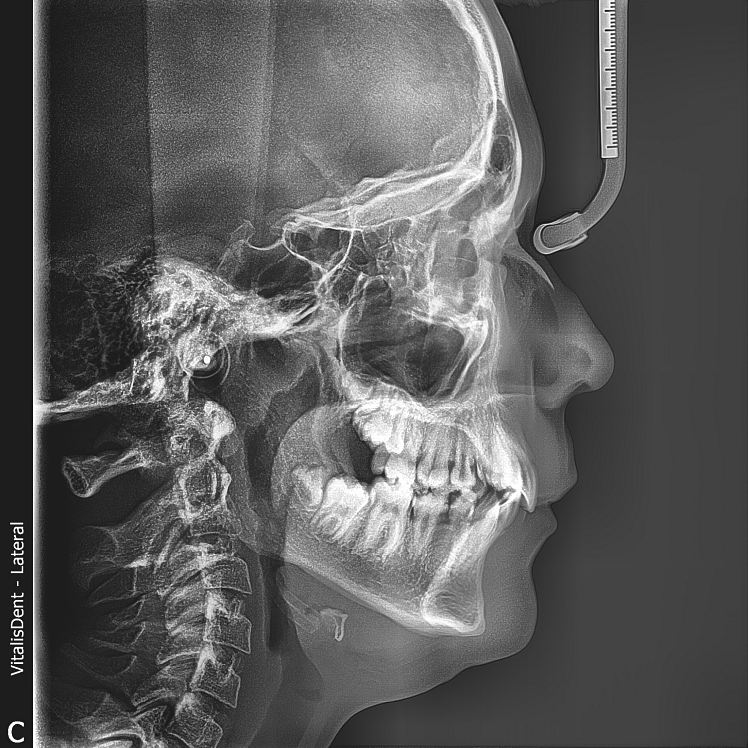

TELERADIOGRAFIE

În special, în ortodonție, cefalometria este utilizată pentru a evalua și diagnostica discrepanțele osoase și dentare, precum și pentru a planifica tratamente ortodontice.